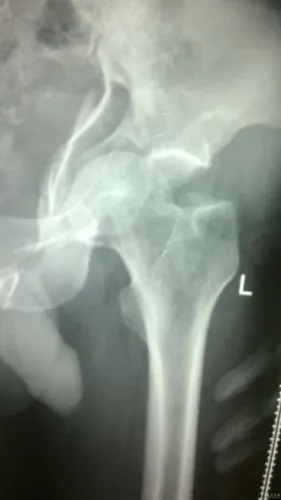

髋关节中心性脱位